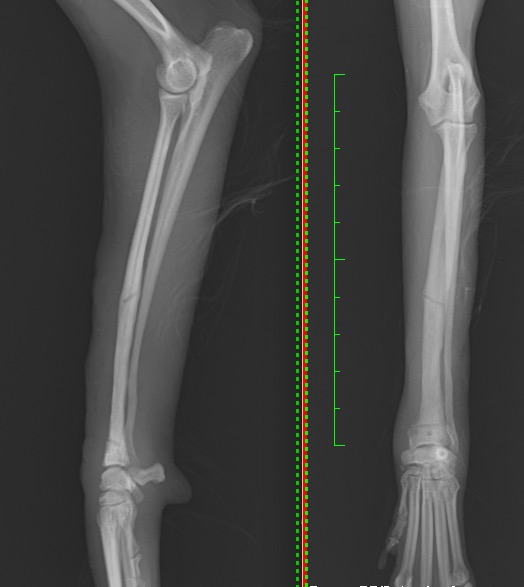

次の写真は最初の手術から1か月後に正面のプレート抜去後になります。

橈骨・尺骨とも癒合が見られます。

小さな穴は正面のプレートを留めていたスクリューが入っていた穴(スクリューホール)です。

1枚目プレート抜去後 Lateral/AP